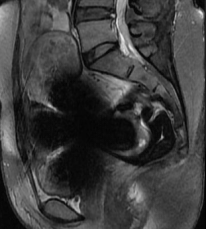

2. 图像质量影响(最常见):这是更实际的问题。节育器中的金属(即使是铜等非铁磁性金属)会在MRI图像上产生金属伪影,表现为图像局部扭曲、变形或出现大片黑影。如果检查部位正好是盆腔、子宫或附件,这些伪影会严重干扰医生观察病灶,可能导致“白做一次检查”,既耽误时间又影响诊断。

图1 部分子宫节育器在MRI上的伪影对结构无法评估